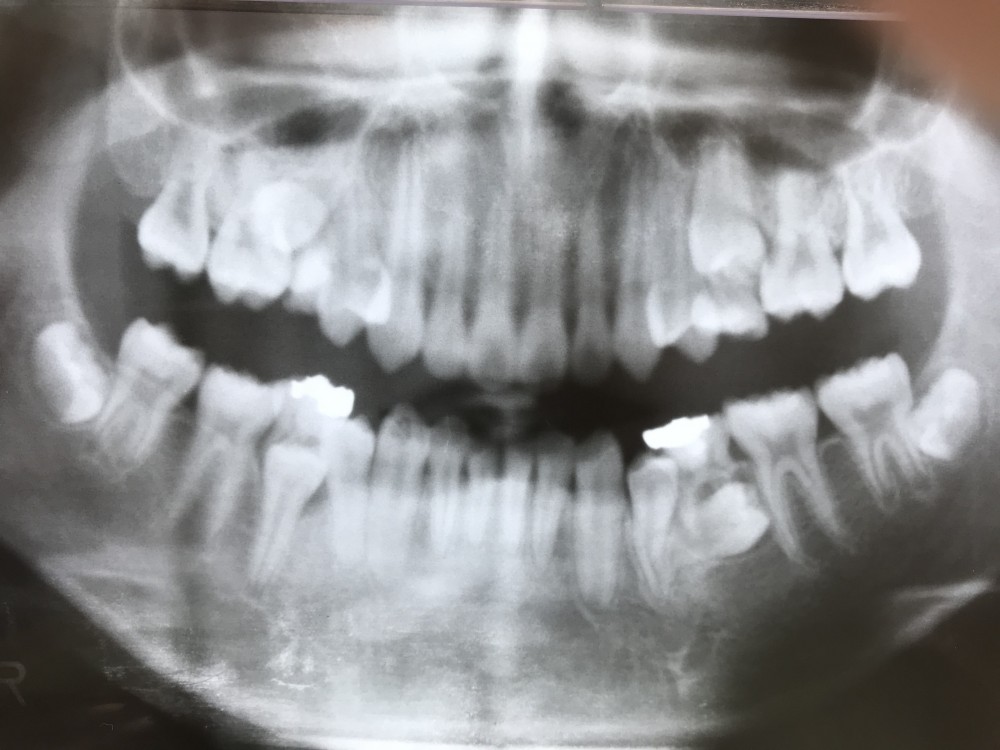

初診時13才0ヶ月、主訴は左下歯茎の腫れ。

下の写真は初診時のものです。